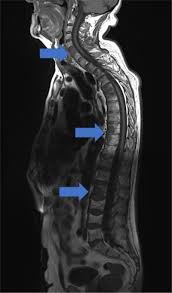

The Use Of Whole Body Mri In Multiple Myeloma Rcp Journals

The Use Of Whole Body Mri In Multiple Myeloma Rcp Journals from www.rcpjournals.org

Multiple myeloma is a cancer of plasma cells, which are white blood cells found mainly in the bone marrow. Find more information on clinical trials that are open for enrollment at mount sinai's center for excellence for multiple myeloma. Multiple myeloma (mm), also known as plasma cell myeloma and simply myeloma, is a cancer of plasma cells, a type of white blood cell that normally produces antibodies. Treatment response, detection of relapse. Related online courses on physioplus. 16,000 new cases and 11,000 deaths. Changing the treatment landscape for hematologic malignancies learn more. In multiple myeloma, when the cancer protein level is up, the normal antibody levels are down. If you still can't find it, please let us know so we can add it!. Tell the radiologist or the radiology technician about your diagnosis before receiving dye injection into. It accounts for approximately 10% of all. Other tests include blood monoclonal immunoglobulin and radiology tests to determine the extent of bone lesions. Spotlight revised international staging system for multiple myeloma: